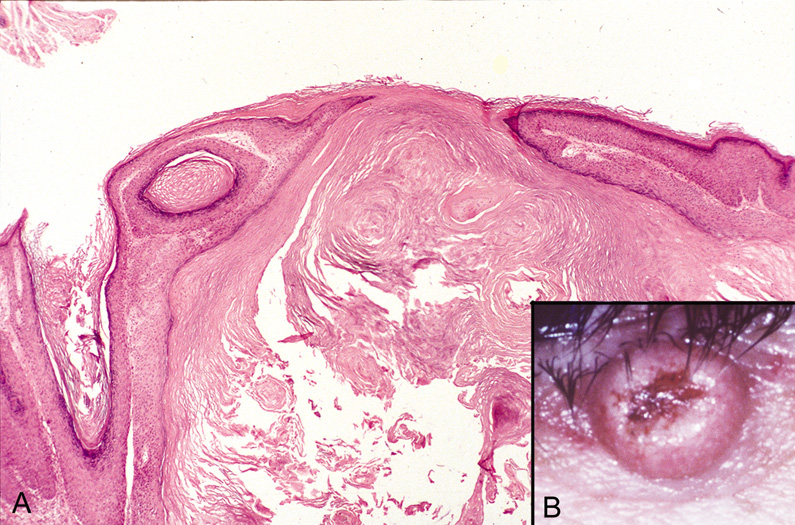

An external hordeolum (stye) (Fig. 4) results from an acute purulent inflammation of the superficial sweat and sebaceous glands or hair follicles of the eyelids, while an internal hordeolum occurs in the meibomian glands within the tarsal plates of the lids. They are characterized histologically by dense inflammation containing neutrophils and foreign body multinucleated giant cells around intact or ruptured appendegeal structures. A chalazion is chronic inflammation of a meibomian gland (deep type) or zeisian sebaceous gland (superficial type) resulting in a clinically firm, painless nodule of the eyelid (Fig. 5A). Histologically, there is deep dermal or subcutaneous suppurative granulomatous inflammation containing neutrophils, plasma cells, lymphocytes, histiocytes, and giant cells in a zonal configuration around central lipid material (see Fig. 5B).

Fig. 5. Chalazion—A. Typical clinical appearance of chalazion. B. Lipogranulomatous reaction with epithelioid cells, lymphocytes, and plasma cells surrounding a central nidus of Meibomian gland secretion. Clear area in center represents lipid material dissolved out during processing of tissue. Giant cells are sometimes seen (hematoxylin and eosin stain). (Photos courtesy of William Morris, M.D.)